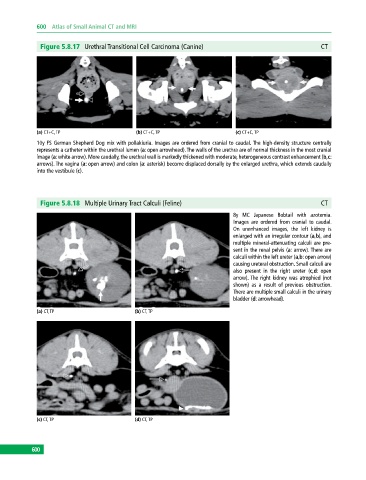

Figure 5.8.17 Urethral Transitional Cell Carcinoma (Canine) CT

(a) CT+C, TP (b) CT+C, TP (c) CT+C, TP

10y FS German Shepherd Dog mix with pollakiuria. Images are ordered from cranial to caudal. The high‐density structure centrally

represents a catheter within the urethral lumen (a: open arrowhead). The walls of the urethra are of normal thickness in the most cranial

image (a: white arrow). More caudally, the urethral wall is markedly thickened with moderate, heterogeneous contrast enhancement (b,c:

arrows). The vagina (a: open arrow) and colon (a: asterisk) become displaced dorsally by the enlarged urethra, which extends caudally

into the vestibule (c).

Figure 5.8.18 Multiple Urinary Tract Calculi (Feline) CT

8y MC Japanese Bobtail with azotemia.

Images are ordered from cranial to caudal.

On unenhanced images, the left kidney is

enlarged with an irregular contour (a,b), and

multiple mineral‐attenuating calculi are pre-

sent in the renal pelvis (a: arrow). There are

calculi within the left ureter (a,b: open arrow)

causing ureteral obstruction. Small calculi are

also present in the right ureter (c,d: open

arrow). The right kidney was atrophied (not

shown) as a result of previous obstruction.

There are multiple small calculi in the urinary

bladder (d: arrowhead).

(a) CT, TP (b) CT, TP

(c) CT, TP (d) CT, TP